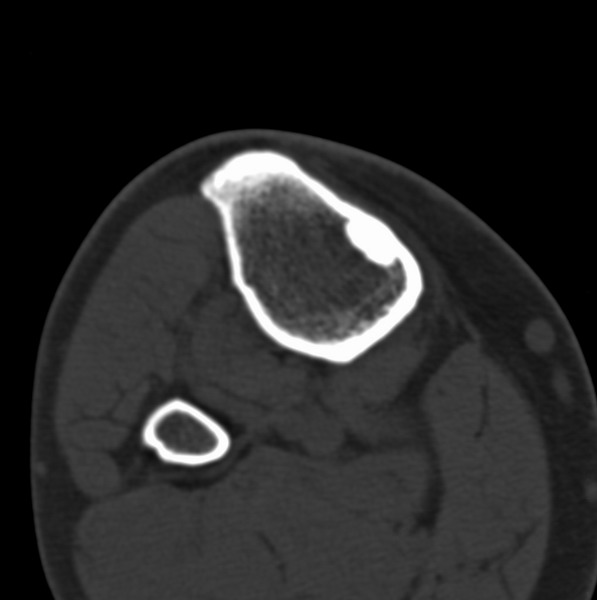

右侧膝关节疼痛一月

男、48

股骨下段、胫骨上段。

1、股骨干骺端病变考虑干骺端纤维性皮质缺损愈后(非骨化性纤维瘤)改变,胫骨近端内生骨瘤(或干骺端纤维性皮质缺损愈后改变);

股骨干骺端病变考虑干骺端纤维性皮质缺损愈后(非骨化性纤维瘤)改变,胫骨近端内生骨瘤(或干骺端纤维性皮质缺损愈后改变);

1、股骨干骺端病变考虑干骺端纤维性皮质缺损愈后(非骨化性纤维瘤)改变,胫骨近端内生骨瘤;

2、骨关节炎,骨质增生,股骨外侧髁退变性囊肿(关节面软骨下囊肿);

股骨干骺端病变考虑非骨化性纤维瘤。